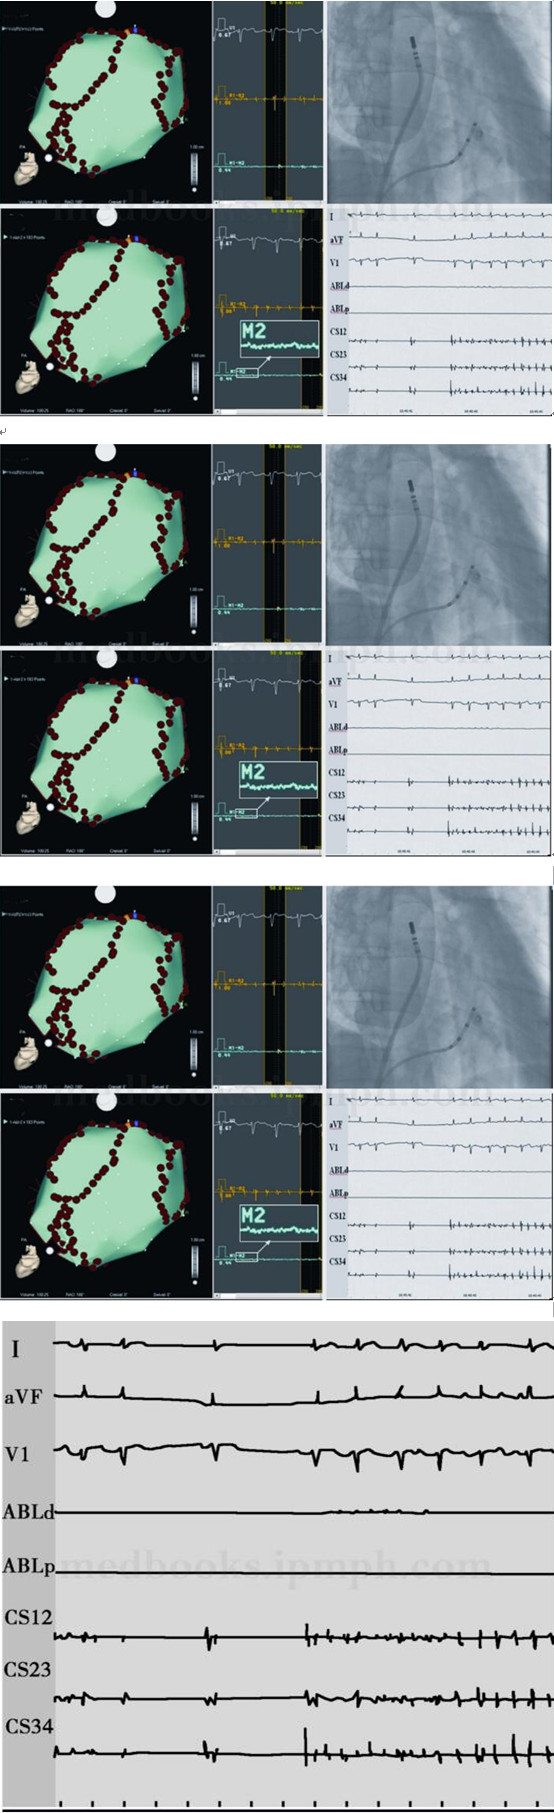

环肺静脉消融:单导管环肺静脉前庭消融,消融设置为功率35W、温控45℃,盐水灌注速度17或30ml/h、单点消融时间为15~30秒加上小范围反复。右侧和左侧环肺静脉前庭消融后肺静脉电位消失(图84‐2),从开始消融记时35分钟实现双侧肺静脉电学隔离,但是房颤没有任何变化,慢性房颤绝大多数有此相似表现。如何进一步消融?电复律后结束或是进一步消融至房颤中止?在这个问题上虽然目前没有共识,但是CFAE消融越来越多地被人们采用。

图84‐2 右侧及左侧肺静脉初始环状消融后肺静脉隔离

左图和右图分别为右侧及左侧肺静脉初始环状消融后消融导管(ABLd,ABLp)在肺静脉内的记录,肺静脉电位消失,证明肺静脉电学隔离,但是从冠状静脉窦记录(CS12,CS23,CS34)可见房颤没有变化,从冠状静脉窦记录的心房周长与消融前比较变化不大

CFAE消融:首先在CFAE记录部位消融,包括左房前顶部、间隔部及二尖瓣环峡部,但是房颤依然,最后在左房顶部最佳CFAE处消融时房颤短暂中止,经2跳窦性心律和2秒房颤之后转复为规律的房性心动过速(图84‐3,图84‐4A)。此CFAE消融导致关键性的转折,如果未标测到此点,而是付之以电复律,规律的心动过速则难以表达出来,更谈不上消融了。因此CFAE消融在慢性房颤导管消融中具有重要意义。

图84‐3 CFAE消融中止房颤

AB图左侧为左心房CARTO解剖构型(后前位),由红色球状点组成的左右2个环分别是左侧和右侧肺静脉环状消融线,AB图的右侧上中下3条记录依次为体表心电图V1(白色)、冠状静脉窦R1‐R2(黄色)和标测消融导管M1‐M2(蓝色)。A图为4个肺静脉隔离后和在其他CFAE部位消融后在顶部蓝点处记录消融,可见R1‐R2快而不规则,仍为典型房颤。B在左房顶部黄点处标测消融(图C为对应X光影像)后房颤转为窦性心律,然后又经2秒房颤转为规律的房扑,周长220ms,即消融过程中的第1个房扑,见图D

规律的房性心动过速的对策:慢性房颤在肺静脉隔离和CFAE消融后出现规律房性心动过速几乎是一种代表性的转归。进一步治疗策略是电复律后结束操作?或是根据拖带等刺激技术确定关键部位并消融?或是根据体表心电图特点判断和消融?对该类心动过速体表心电图通常不能准确判断机制,电复律则会丧失判断心动过速机制的机会,拖带等技术有一定帮助,但是还有可以使我们更加明确心动过速机制的方法,即现代电解剖三维标测技术,该技术在此领域有独到之优势,首先对左心房进行激动顺序标测,显示左房后间隔部位激动最早(图84‐5A),是该部位局灶房速吗?之后对右心房进行了激动顺序标测,显示为CTI依赖的右房房扑(图84‐5B),采用相同参照整合后可见左房为被动表现(图84‐5C)。沿CTI消融不超过1cm长度房扑中止(图84‐4B、84‐4C),并且峡部传导阻滞,冠状静脉窦刺激信号到低右房间期为163ms(图84‐4D)。

图84‐4 CTI依赖房扑消融过程

A图为CTI依赖房扑12导联ECG,B图为在CTI消融的X线影像,C图可见CTI消融过程中房扑中止,D图显示起搏冠状静脉窦S‐LRA间期(163ms)

图84‐5 CTI依赖右房房扑

在左侧肺静脉前庭后顶部CFAE处消融时房颤一过性中止并转为心房扑动(图84‐3),周长220ms,A图为左房激动顺序标测,左后间隔部位激动最早,B图为右房激动顺序标测,为CTI依赖房扑,C为左右心房共同参照整合图形,可见左房被动